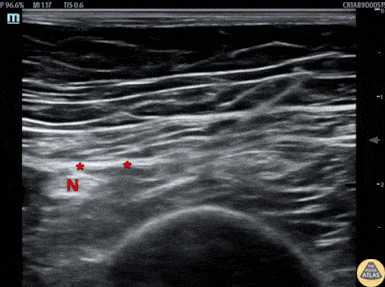

An elderly female presented with hip pain after an unwitnessed fall at her nursing home, and was found to have a shortened, rotated lower extremity, and after a broad workup was found to have a proximal femur fracture. To aid in pain control, a fascia iliaca block was performed under US guidance. The block is shown here, with the needle entering from the lateral aspect and injecting anesthetic in the fascia iliaca fascial plane. As seen by the very superficial femoral cortex, this 90s year old female was quite sarcopenic, so the normal muscular sonoanatomy is limited. The fascial spread seen in this clip helped to confirm appropriate placement of anesthetic. This patient was able to be admitted for surgery and had significant pain relief. Dr. James Sutton, PGY3 Denver Health Residency in Emergency Medicine